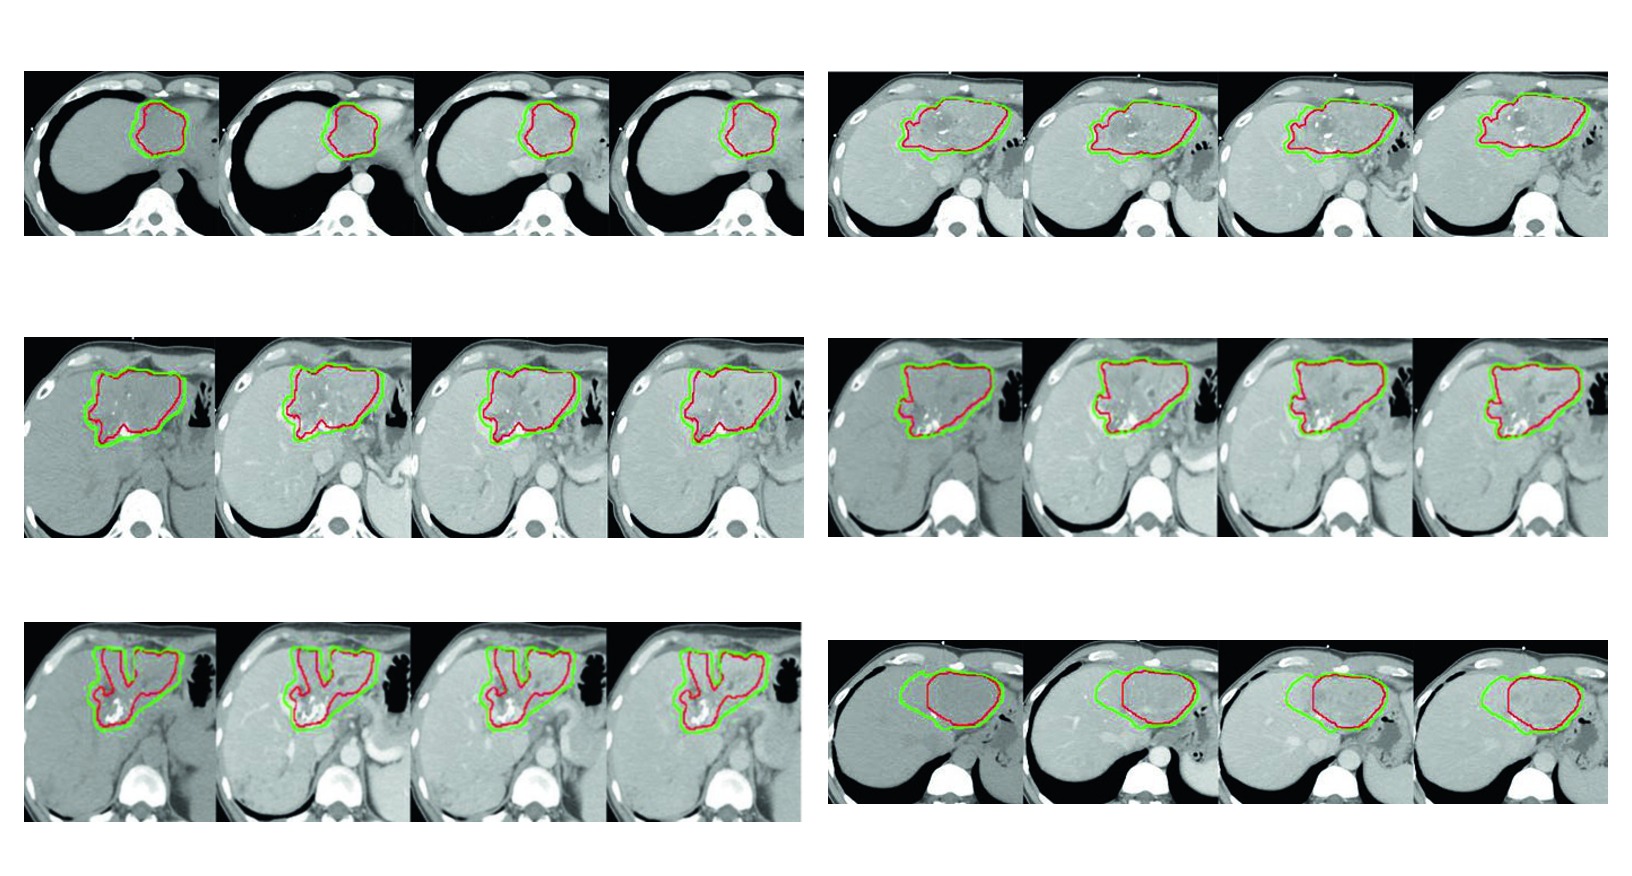

As quatro figuras do capitulo funcionam como exemplos aplicados da mesma logica. Todas usam simulacao multiphasica com coordenacao de apneia para imobilizacao do figado. Todas mostram GTV em vermelho e CTV em verde. E todas deixam claro que a margem muda quando entram em cena trombo tumoral, zona previamente ablada, area embolizada ou risco de extensao ao longo do vaso.

Figura 17.4

No quarto caso, o HCC refratario ao sorafenibe com progressao de tromboses em veia porta e veia hepatica media resume bem o capitulo. O CTV inclui o tumor contrastado, o GTV em vermelho e uma margem tridimensional de 5 mm dentro do limite hepatico. Aqui o livro mostra que, mesmo diante de invasao vascular importante, a expansao ainda precisa respeitar a fronteira anatomica do figado.

Lidas em conjunto, as figuras defendem uma mensagem muito consistente. A margem intraparenquimatosa cobre risco adjacente dentro do figado. A margem intravascular aparece quando o trombo tumoral faz parte real do problema geometrico. A zona ablada ou embolizada entra no volume quando o caso exige, nao por automatismo. Esse e provavelmente o trecho mais didatico do capitulo para quem precisa justificar o desenho final do volume em reuniao clinica ou revisao de caso.